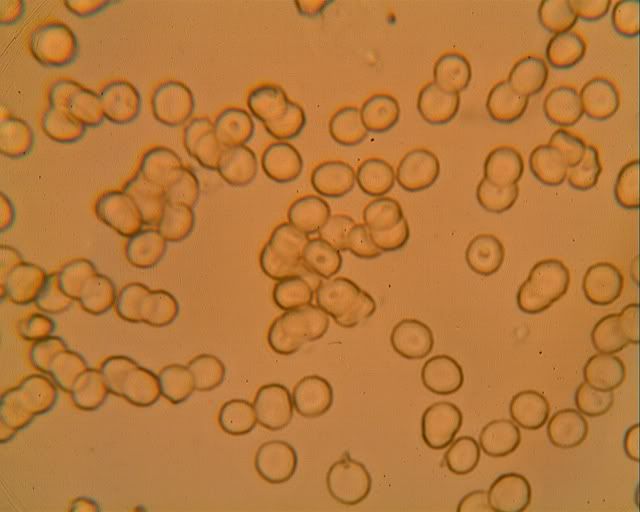

Becky the diabetic's blood at 800x. |

Red blood cells that are not red? Doesn't make any sense to me. One would think there is a lack of iron in them. But the person they came from isn't anemic. Any ideas? |

Yep, they aren't circulating any more. Might have gone all blue blood on you. |

I havent been using my microscope lately and so havent been looking at red blood corpuscles to see how much pink is visible. Maybe the red color is so weak because one's looking through such a thin layer of protoplasm - about two microns max judging by the (7.6 micron) diameter and shape. |

You can get a special dye that will dye them red and increase contrast.... Usually a Wright's stain P.S. You can get the stain cheaper than this. This is a 1L bottle keep in mind :)   |